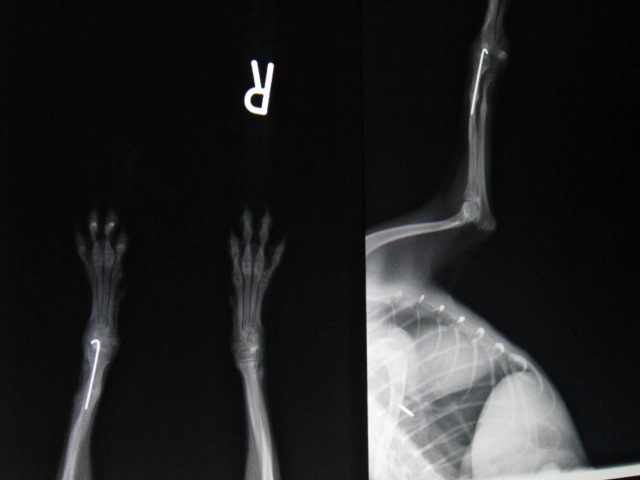

術前のレントゲンです。

左前肢橈尺骨骨折です。